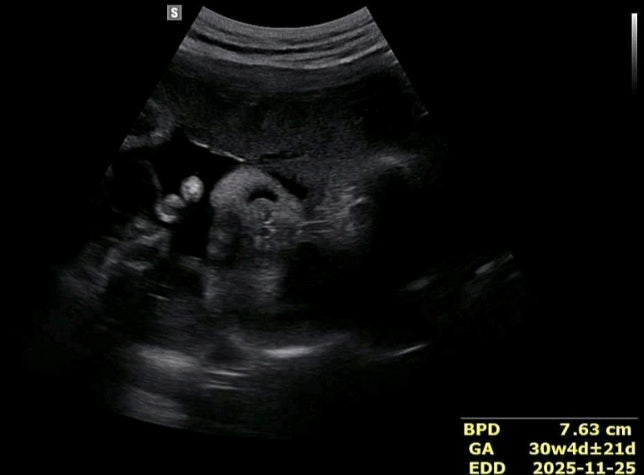

[임신] 30주차 배가 내려간듯해 병원 다녀왔어요!!

12일만에 산부인과 또 방문..ㅋㅋㅋㅋㅋㅋㅋㅋㅋ 30주여서 이제 배ㅣ도 제법 나왔는데 아래쪽으로 쳐져보이...